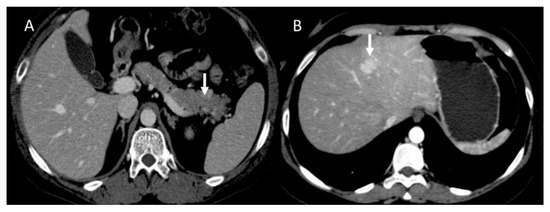

Figure 2.

CT evaluation during portal phase of pancreatic NEN ((A): arrow) with liver metastasis ((B): arrow).

Figure 3.

CT evaluation during arterial phase of pancreatic NEN ((A): arrow) with liver metastases ((B): arrow).